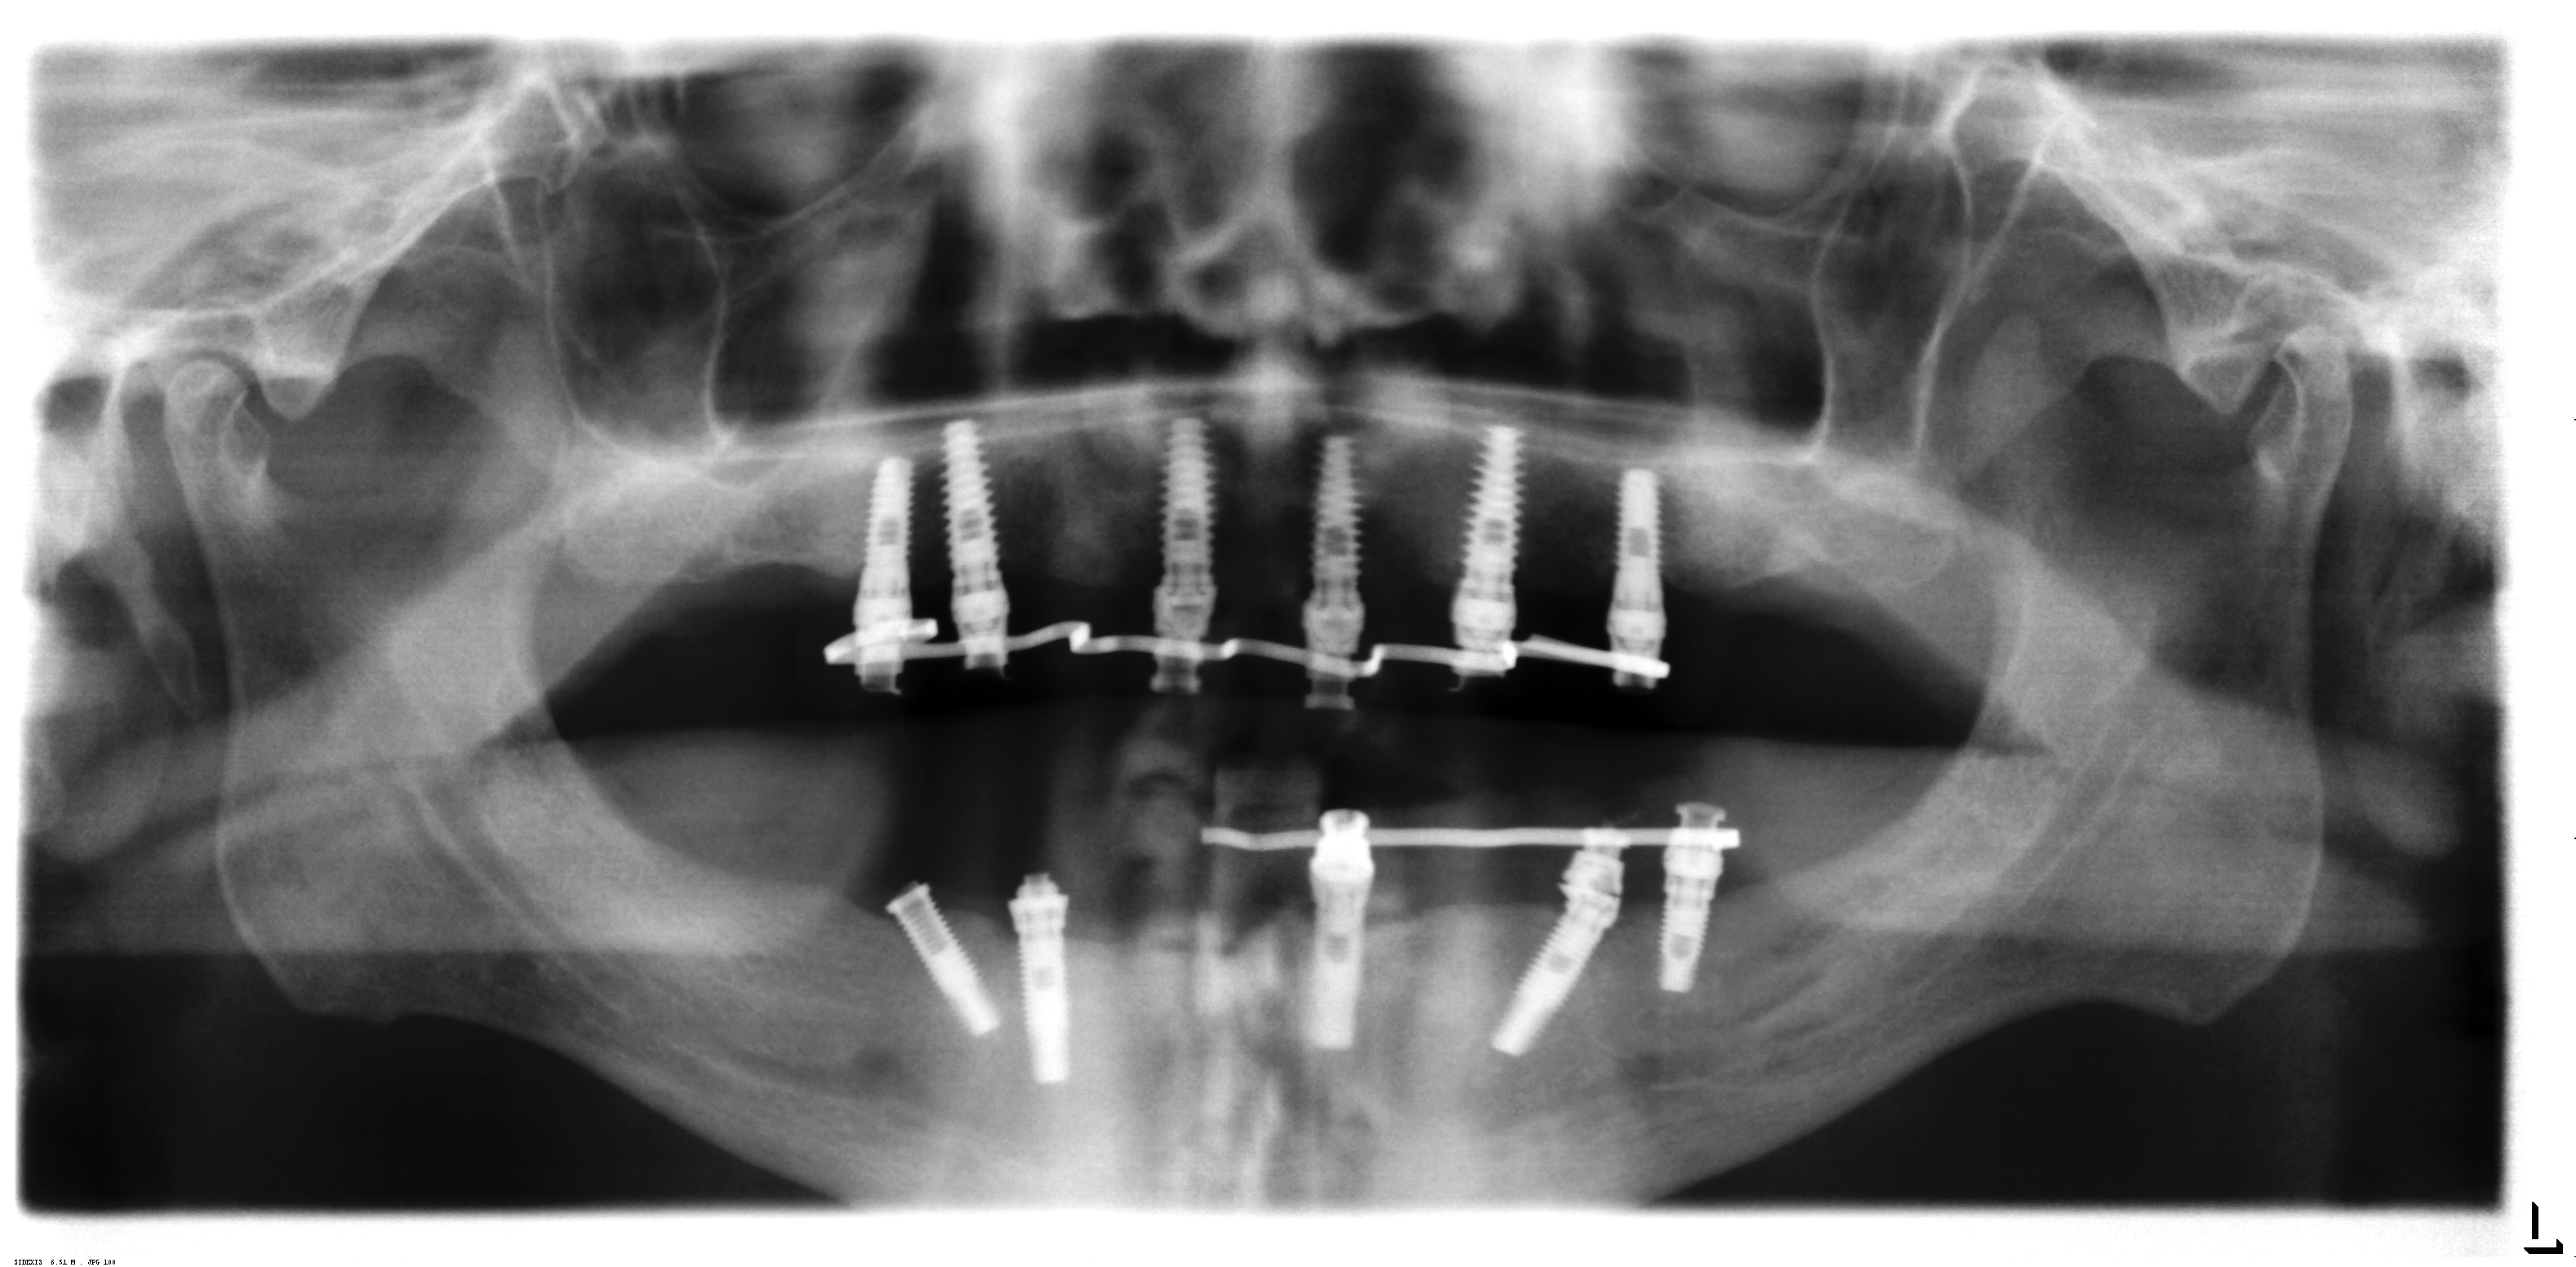

BUENOS DÍAS: Tengo el caso de un paciente con unos implantes colocados en i-dental hace unos 3 años.Hay que rehabilitarle max sup e inferior y no consigue ni marca ni [...]